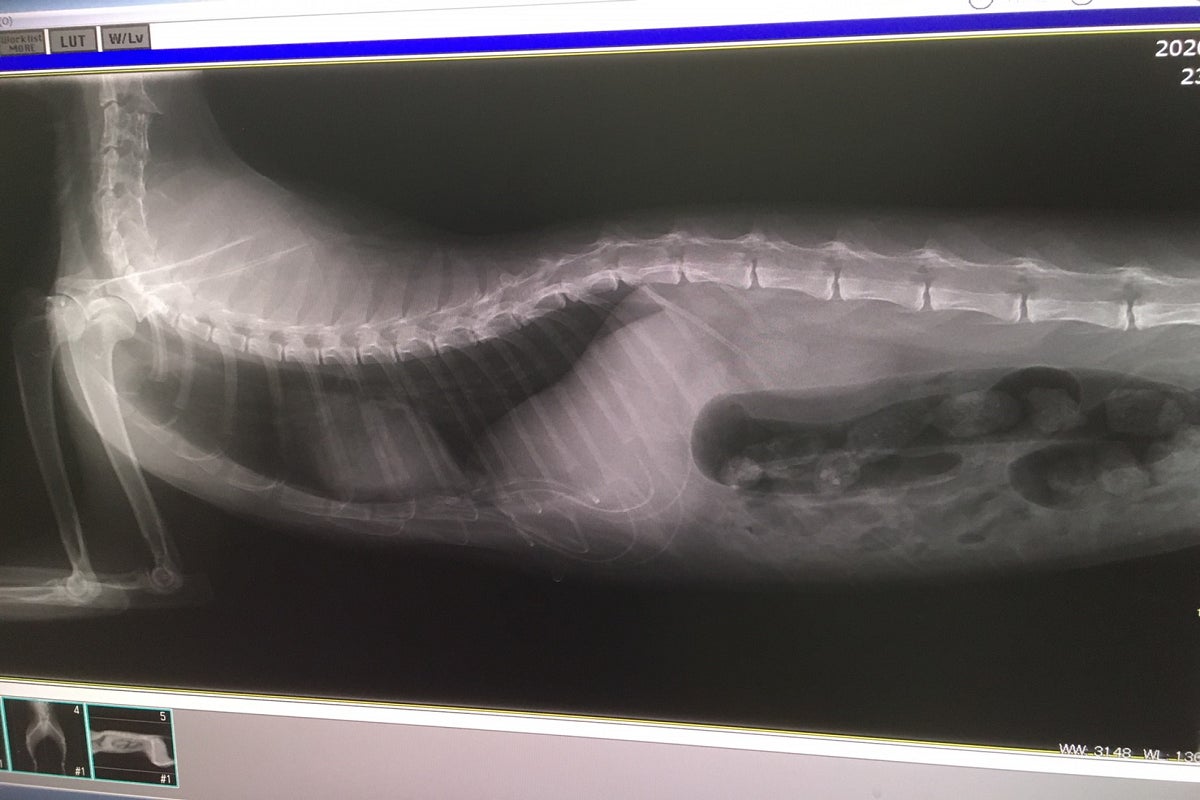

レントゲンでの診断の結果

骨盤骨折(腸を圧迫して排便できないかもしれない)

脛骨複雑骨折

重度の貧血

膿が溜まっている。

獣医師の診断は虐待ではなく事故だろう。膿の様子から事故してから1週間

くらいは経過しているだろう

金属アレルギーがあるかも?抗生剤が効かない!壊死が進むと断脚になるかも!

敗血症にならないように細心の治療。

頸椎の複雑骨折の完治、並びに腰椎骨折の経過観察、下半身マヒ回避治療、感染症予防の治療